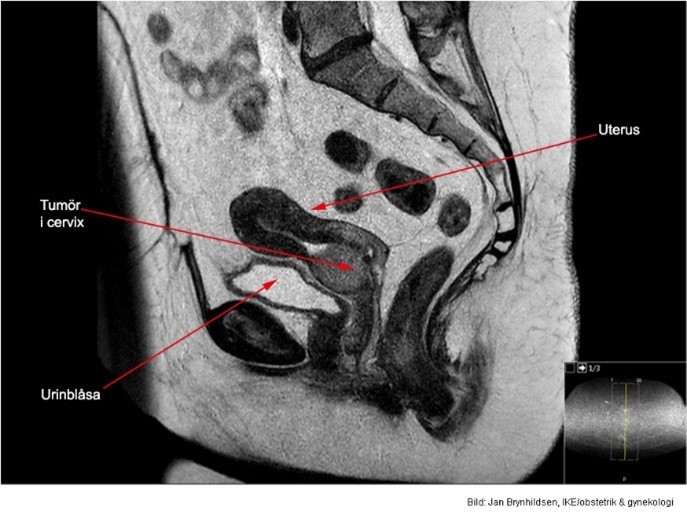

Vad visar bilden?

Invasivt växande skivepitelcancer.

3x4 cm stor cervixtumör utan hållpunkter för spridning.